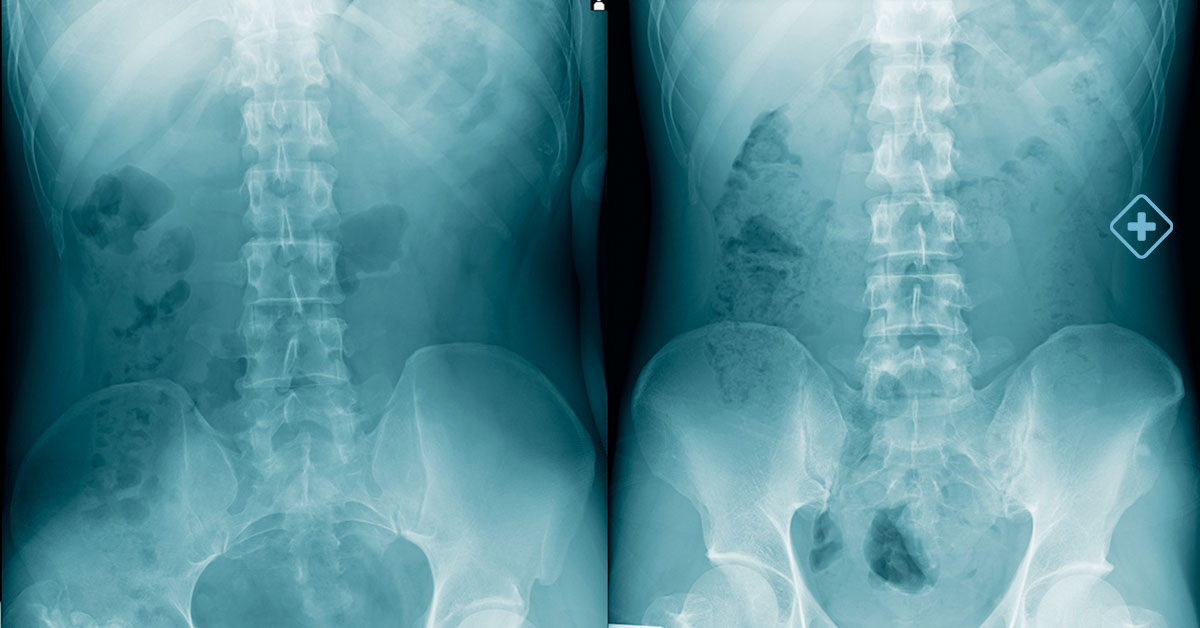

Before undergoing back surgery, the patient should undergo a thorough evaluation by a neurosurgeon.

This may include advanced diagnostic tests, such as MRIs, CT scans, and X-rays, which will help the specialists fully understand the nature and extent of the problem.